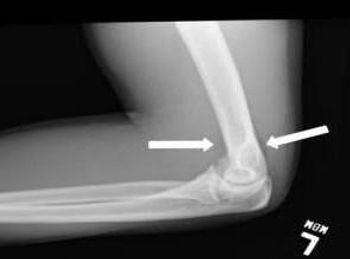

Images of Achilles tendon injuries, rotator cuff tears, FOOSH (fall on outstretched hand) injury, superficial abrasion, Lisfranc joint injury, and avulsion fracture.